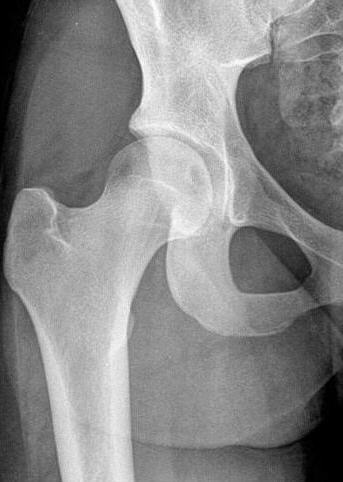

rechts: Beachten Sie die rundlichen Aufhellungen im entrundeten Femurkopf und in der Gelenkpfanne, die subchondrale Sklerosierung und den engen Gelenkspalt

Vergleichen Sie die linke (physiologische) Aufnahme mit der rechten (pathologischen) Aufnahme